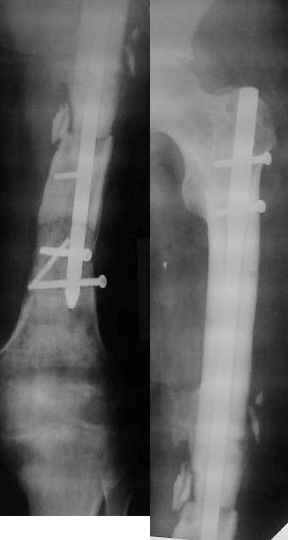

Неудачный остеосинтез пластиной: поломка винтов, миграция фиксатора. После удаления пластины сформировался гипопластический ложный сустав нижней трети бедренной кости, укорочение н/к 5 см. Выполнялся дистакционный остеосинтез аппратом Илизарова на штифте. Зона ложного сустава "не открывалась". Через 10 месяцев, когда даже регенерат полностью перестроился, консолидации в зоне ложного сустава не наступило, несмотря на стабильную фиксацию и постоянную компрессию(штифт+аппрата на 4 кольцах).